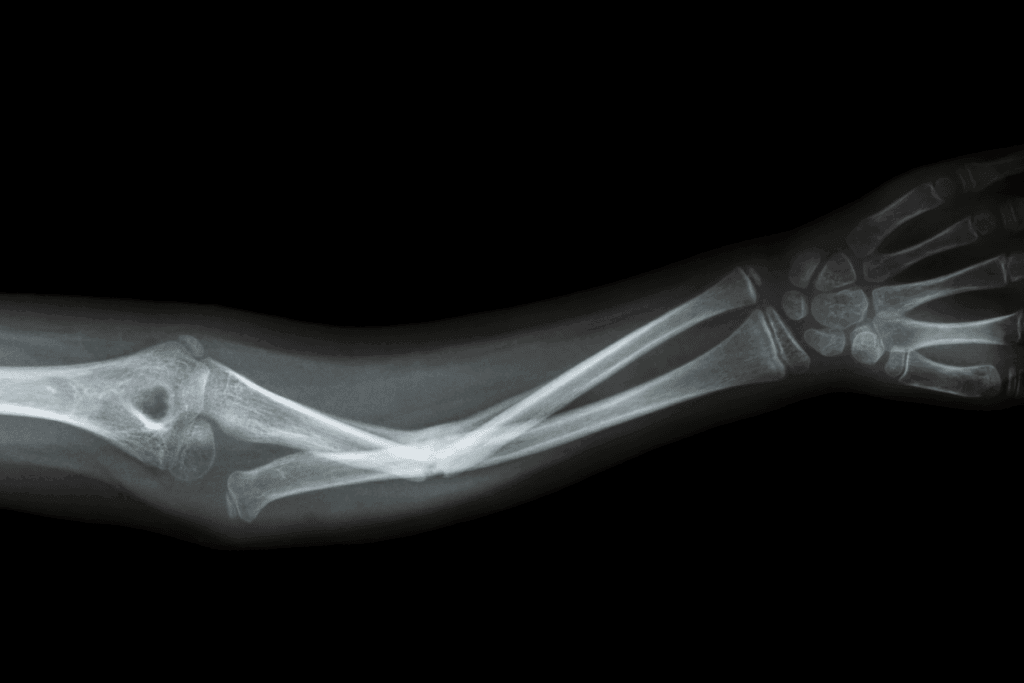

The greenstick fracture looks like a green branch breaking. It’s a common fracture in kids. This fracture happens when a bone bends and partially breaks, unlike a complete break.

Children’s bones are more flexible and less likely to break completely. This is why greenstick fractures are common in them.

Common in Children

Greenstick fractures are common in children because their bones are growing and flexible. When a force, like a fall, is applied, the bone bends and cracks on one side. This is unlike adult bones, which tend to break completely.

This fracture often occurs in the forearm. Kids usually use their arms to break their fall.

Healing Process

The healing process of fractures like greenstick fractures is usually straightforward. Children’s bones can grow and heal quickly. This means greenstick fractures often heal fast and without major issues.

Treatment usually involves a cast to help the bone heal. Sometimes, the bone needs to be gently moved back into place. It’s important for a healthcare provider to monitor the healing process to avoid long-term problems.